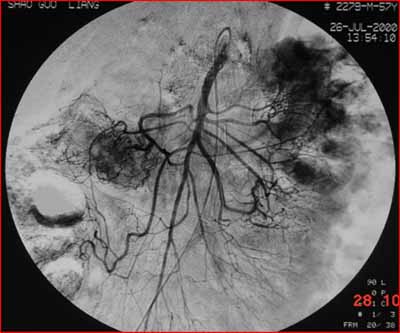

(結(jié)腸動(dòng)脈造影:腫瘤染色明顯。通過(guò)造影明確供血?jiǎng)用},進(jìn)行腫瘤區(qū)域的化療灌注。)